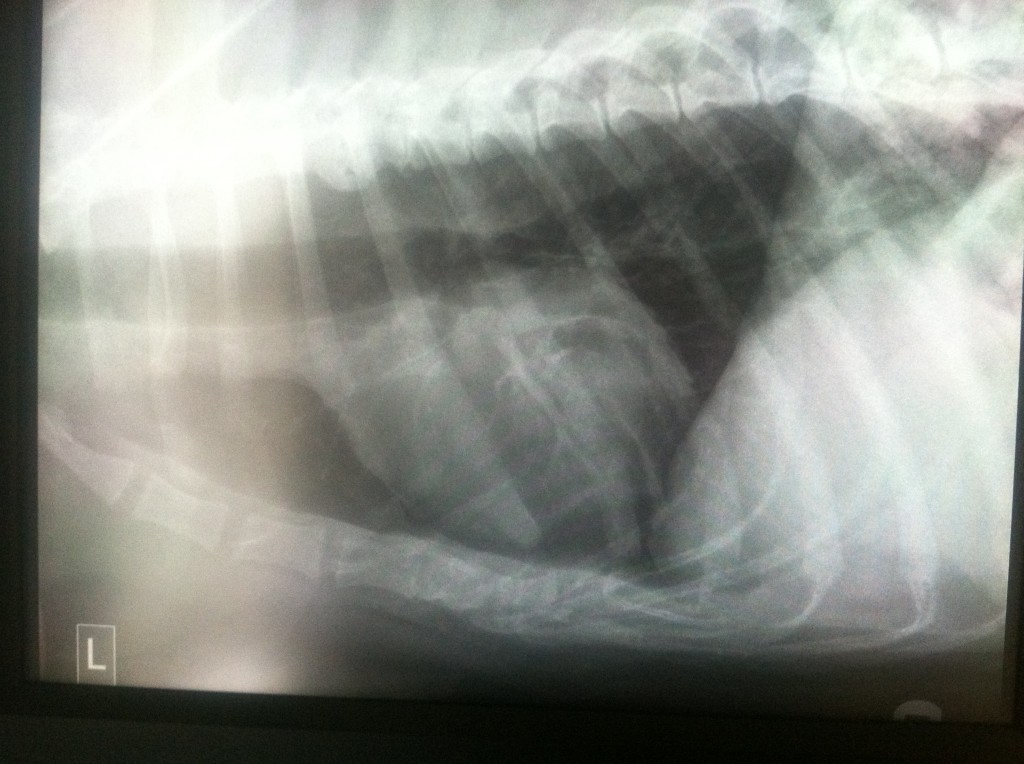

WEEK 1

I am not going to act like I know a lot about what these x-rays are showing because reading x-rays is not my forte, but I can tell you what was explained to me:

Pleural effusions appear on chest X-rays as white space at the base of the lung. Pleural effusion obscures the silhouette of the heart

It’s really hard to see Sherman’s lung in these small pictures but you can see the white space in the top two pictures and his heart has obvious loss of details compared to the 3rd x-ray.

Pnuemothorax means air in the chest cavity.

In the first 2 pictures there is mild pneumothorax in Sherman’s chest cavity.

Again, it’s hard to see in these pictures. Taking x-rays of the chest of a giant breed dog is no easy task. The x-rays plates just aren’t big enough to accommodate them.